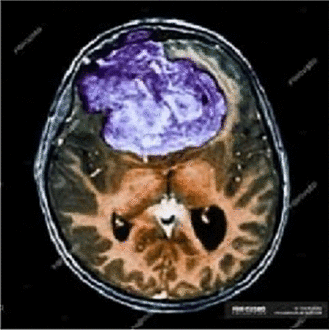

Cipher image 1